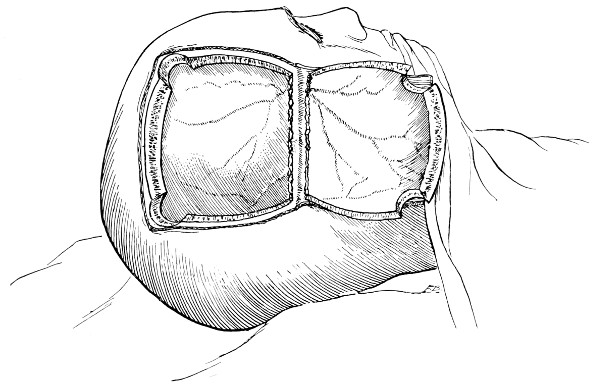

Fig. 18. Second Stage in the Formation of an Osteoplastic Flap. The bone-flap turned down and the dura mater exposed.

Fig. 19. Third Stage in the Formation of an Osteoplastic Flap. The dural flap turned down and the brain exposed. Note the relation of the scalp, bone, and dural incisions to one another.

The dura is now separated from the bone along the line of the two vertical incisions, and the visceral blade of de Vilbiss’s forceps insinuated beneath the bone, starting at one trephine-hole and working downwards to the lower limit of the incision. It is essential that the operator should be satisfied with the ‘morcellement’ of small portions of bone at each bite of the instrument. At the lower end of each[28] of the vertical incisions the forceps is directed inwards for 14 to 12 inch so as to weaken the base of the flap.

To lift up the osteoplastic flap, a stout elevator or spatula is introduced beneath the bone at its upper part, leverage applied, and, as soon as sufficient elevation has been attained, the dura mater carefully separated from the whole of the under aspect of the flap. The flap is then grasped at its upper part with both hands and, with a quick but forcible jerk, broken across at its base, the assistant at the same time aiding the correct linear fracture of the bone by a flat spatula applied to the outer aspect of the base of the flap. Insomuch as the flap is most usually framed in the parieto-temporal region—for the exposure of the motor area—the base of the flap, being formed from the squamous portion of the temporal bone, is comparatively weak. Fracture is then readily obtained. Under other circumstances the base may be sufficiently weakened by the application of the de Vilbiss forceps or by the use of the Gigli saw.

The bone-flap is thrown back and enveloped in gauze. Its basal region is examined for a possible injury to meningeal vessels. In the event of such complications the bleeding vessel is clipped, ligatured, or underrun. Possibly some branch of the anterior division of the middle meningeal artery, running in an osseous canal, may require to be controlled by foraminal occlusion—with a wooden match, bone peg, cotton-wool, or aseptic wax.

In comparing the relative advantages and disadvantages of craniectomy and craniotomy, although there are certain definite contra-indications to the latter method, yet craniotomy should always be carried out when the surgeon desires to expose a large surface area of brain, more especially in the exposure of a tumour diagnosed to lie in relation to the motor cortex. Even if the operator should be unsuccessful in his exploration, or, if finding the tumour, should deem it irremovable, the dura can be sewn up and the bone-flap replaced, resting on its bevelled edge, with little defect in the skull and a normal surface contour.

The three main disadvantages to craniotomy are as follows:—(1) the operation can seldom be done under much less than thirty minutes; (2) there is some slight risk of complication through injury to the middle meningeal artery; and (3) the dura mater may be so[29] adherent to the bone as to be torn in the process of flap-elevation. Time, however, is usually of little importance; bleeding from the middle meningeal artery may be controlled, and dural lesions may be avoided by careful technique. In general, the advantages of osteoplastic resection greatly outweigh the disadvantages.